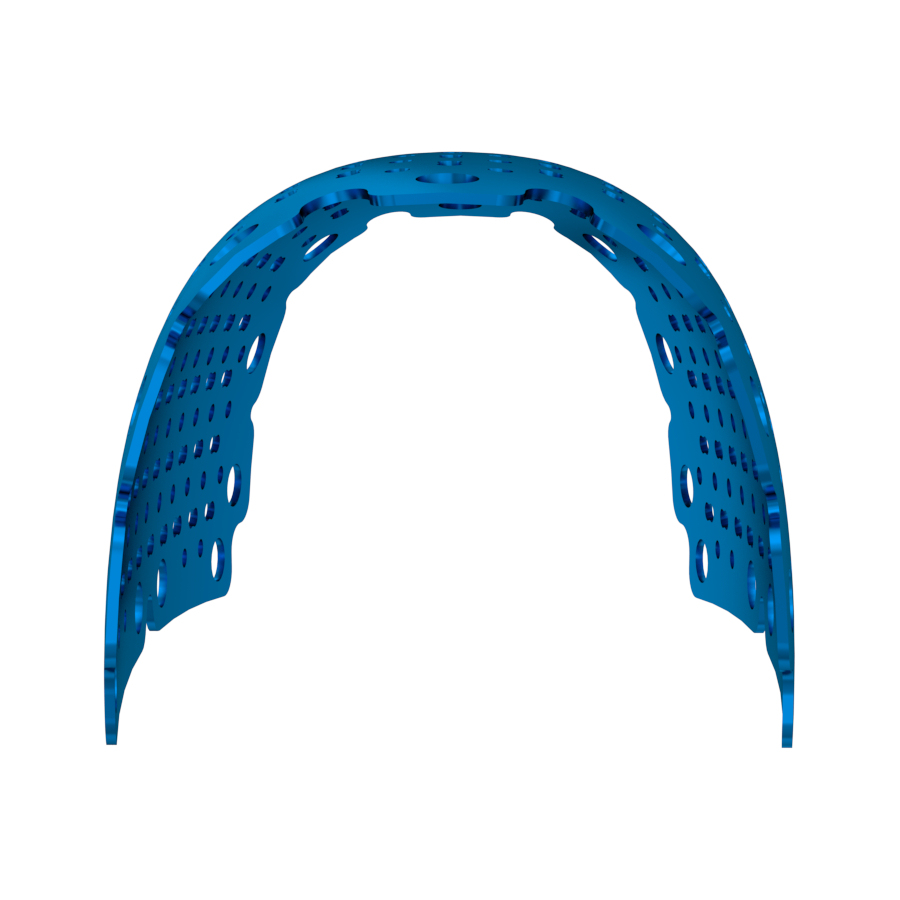

Our Titanium Mesh Membrane is designed to offer optimal support in guided bone regeneration (GBR) procedures, combining structural stability with excellent adaptability. The ultra-thin, anatomically contoured design allows for a comfortable fit and easy surgical handling, while maintaining strong support for the defect area. It can be easily trimmed and shaped to match various bone contours, making it a reliable and versatile choice in both simple and complex cases.

H Type

-

Proximal Width: —

-

Buccal Width (BW): 20 mm

-

Buccal Length: 11 mm

-

Lingual Height: 11 mm

-

Thickness: 0.2 mm